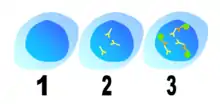

The human body has many defense mechanisms against pathogens, one of which is humoral immunity. This defence mechanism produces antibodies (large glycoproteins) in response to an immune stimulus. Many cells of the immune system are required for this process, including lymphocytes (T-cells and B-cells) and antigen presenting cells. These cells coordinate an immune response upon the detection of foreign proteins (antigens), producing antibodies that bind to these antigens. In normal physiology, lymphocytes that recognise human proteins (autoantigens) either undergo programmed cell death (apoptosis) or become non-functional. This self-tolerance means that lymphocytes should not incite an immune response against human cellular antigens. Sometimes, however, this process malfunctions and antibodies are produced against human antigens, which may lead to autoimmune disease.[3]

The mechanism of antibody production in Sjögren's syndrome is not fully understood, but apoptosis (programmed cell death) and molecular mimicry may play a role.[12] The Ro and La antigens are expressed on the surface of cells undergoing apoptosis and may cause the inflammation within the salivary gland by interaction with cells of the immune system. The antibodies may also be produced through molecular mimicry, where cross reactive antibodies bind to both virus and human proteins. This may occur with one of the antigens, Ro or La, and may subsequently produce antibodies to other proteins through a process known as epitope spreading. The retroviral gag protein shows similarity to the La protein and is proposed as a possible example for molecular mimicry in Sjögren's syndrome.[12][20]